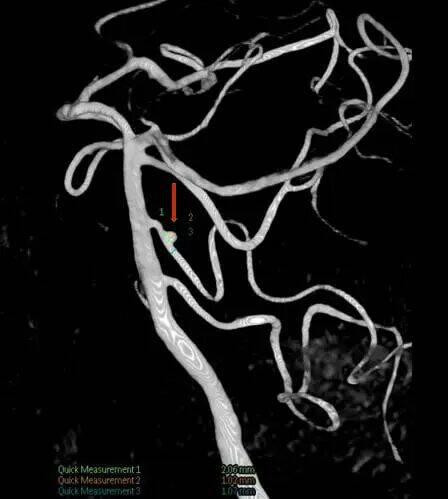

这一手术入路堪称神经外科手术的“高难度赛道”:手术区域深窄,视野暴露受限,术中操作空间极小,稍有不慎就可能损伤面听神经引发面瘫、听力障碍,或触碰脑干导致呼吸循环紊乱,手术风险极高。为确保手术万无一失,团队术前反复研读影像学资料(图1),并急诊先由主治医师张晓东、徐坤和耿仁强行脑血管造影(图2),依托神经介入指引精准标记出动脉瘤的位置、大小及与周边组织的毗邻关系;争分夺秒完善相关准备工作后行开颅动脉瘤夹闭术,术中在高倍手术显微镜下,以毫米级精度仔细分离蛛网膜粘连,小心避开神经血管“禁区”,精准选择适配的动脉瘤夹,成功将动脉瘤颈完全夹闭(图3术中动脉瘤夹位置)。术后复查头颅CT(图4)显示,动脉瘤夹位置精准,动脉瘤无残留显影,周围血管神经未受任何损伤。

术前脑血管DSA影像显示,红色箭头所指为小脑下前动脉瘤瘤体;